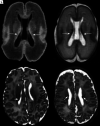

Fig 2.

HPI. T2-weighted MR images through the mid (A) and low (B) basal ganglia level in an infant born at 29 weeks and imaged at 44 + 6 weeks. There is right-sided HPI with formation of a porencephalic cyst lined with low signal intensity consistent with previous hemorrhage (arrow, A), a paucity of low T2 signal myelin in the right PLIC compared with the left (arrowheads, A), and ipsilateral basal ganglia and thalamic atrophy (arrowheads, B). This infant had a motor impairment at 20 months.